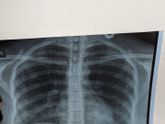

У меня правосторонняя нижняя доля

У меня пневмония правосторонняя нижняя